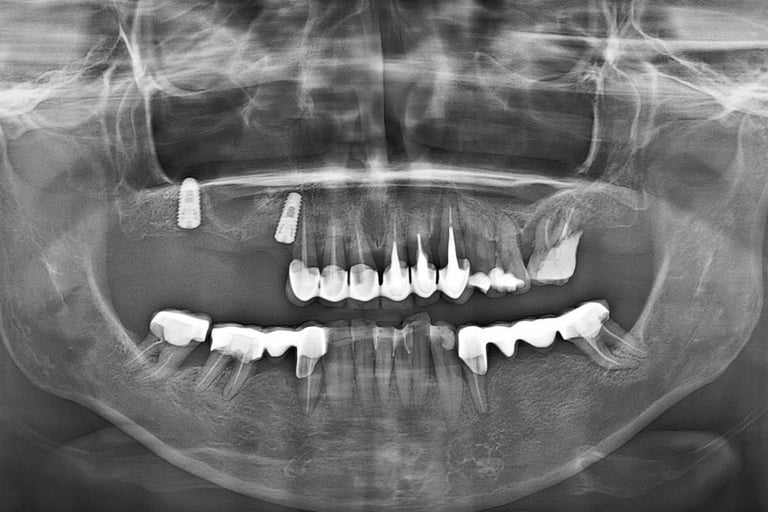

Reabilitare implantara in cazul unor dinti restanti irecuperabili, cu mobilitate severa. Dupa extractia atraumatica a dintilor compromisi, tratamentul continua cu inserarea implanturilor dentare. In prealabil, in urma cu 6 luni s-a realizat aditie osoasa prin sinus lift extern la nivelul cadranului II, tehnica chirurgicala care ne-a permis inserarea implanturile posterioare.

Inserare 2 implanturi in cadranul III si un implant inserat post-extractional in cadranul IV